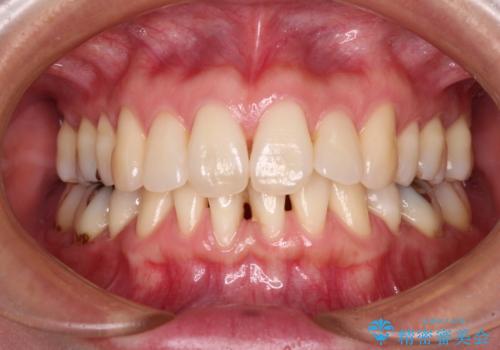

- 矯正治療により下の前歯の歯肉が退縮してしまい、根が見えていることが気になるとのことで来院された患者様です。

歯肉退縮に対して、上顎からの結合組織移植術(CTG)により、歯根の被覆を行うとともに、歯肉の厚みを増すことで将来の退縮リスクを抑制することとしました。

歯と歯と歯肉の間にある三角形の隙間(ブラックトライアングル)は歯肉移植では改善できないため、根面被覆できる量に限界がありましたが、最大限回復させることができました。